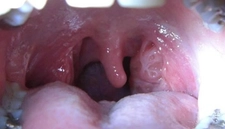

Boğaz Ağrısı ve Tahrişine Ne Tür Çözümler Fayda Sağlar?Boğaz ağrısı, birçok bireyin yaşamında karşılaştığı yaygın bir rahatsızlıktır. Genellikle soğuk algınlığı, grip, alerjiler veya enfeksiyonlar gibi durumlarla ilişkilendirilse de, boğazda tahriş ve ağrıya sebep olan pek çok faktör bulunmaktadır. Bu makalede, boğaz ağrısı ve tahrişine yönelik etkili çözüm önerileri ele alınacaktır. Boğaz Ağrısının NedenleriBoğaz ağrısının birçok olası nedeni vardır. Bu nedenler arasında şunlar bulunmaktadır:

SonuçBoğaz ağrısı ve tahrişi, çeşitli nedenlerden kaynaklanabilir ve bu durumun tedavisi kişiden kişiye değişiklik gösterebilir. Doğal yöntemler, tıbbi tedavi seçenekleri ve yaşam tarzı değişiklikleri, boğaz ağrısını hafifletmek için etkili çözümler sunmaktadır. Ancak, belirtiler uzun süre devam ederse veya şiddetliyse, bir sağlık uzmanına başvurmak önemlidir. Bu sayede, altta yatan nedenler belirlenerek uygun tedavi yöntemleri uygulanabilir. |